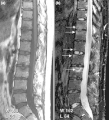

Magnetic resonance images of sacroiliac joints. Shown are T1-weighted semi-coronal magnetic resonance images through the sacroiliac joints (a) before and (b) after intravenous contrast injection. Enhancement is seen at the right sacroiliac joint (arrow, left side of the image), indicating active sacroiliitis.